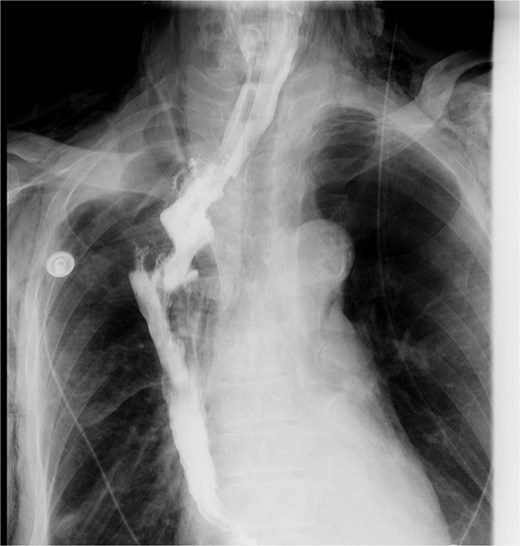

A concise illustration of the disease progression is presented in Fig. 1. A 67-year-old male underwent minimally invasive Ivor Lewis esophagectomy on Day 0, with postoperative confirmation of midesophageal squamous cell carcinoma (T1bN1M0). Follow-up imaging 1 week postsurgery showed no complications (Fig. 2). The patient resumed oral intake without discomfort and was discharged on Day 54.

Upper gastrointestinal series performed during postoperative week 1.